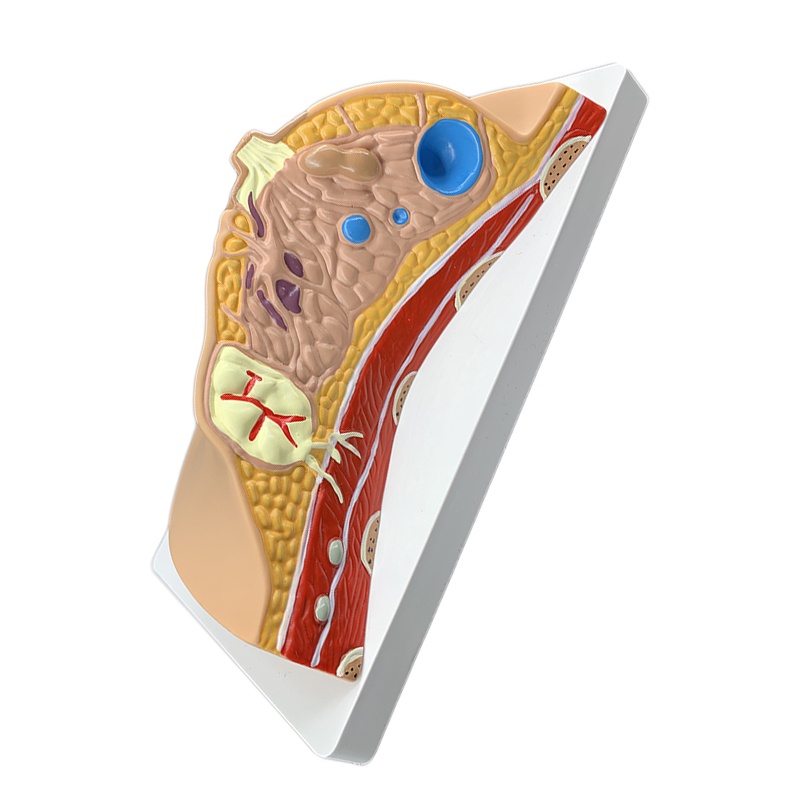

Median Section of Human Female Breast Cancer Anatomical Model Cyclomastopathy Breast Cancer Anatomy Model Medical Study